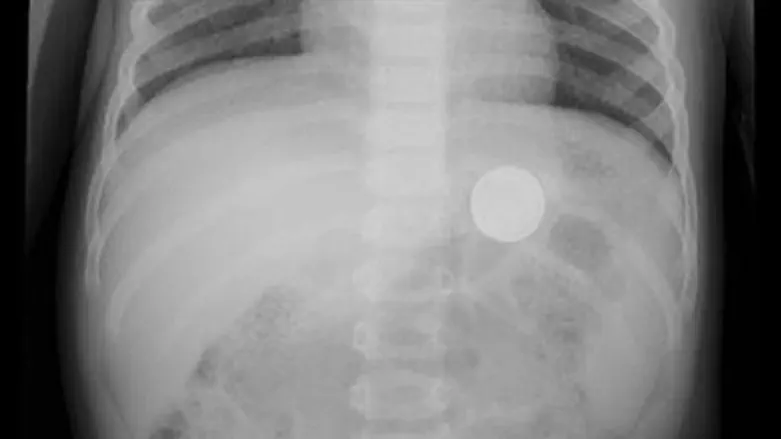

ביום שלישי הובהל פעוט בן 15 חודשים אל מיון ביה"ח "רות" לילדים ברמב"ם, אחרי שהוריו דיווחו כי הוא בלע סוללה. מתוצאות בדיקות הדימות שנעשו בביה"ח עלה כי בשל גודלה של הסוללה, היא נתקעה בוושט, מצב המעמיד את הפעוט בסכנת חנק.

תחת טשטוש, הוציא צוות יחידת גסטרו ילדים את הסוללה בתהליך הנקרא גסטרוסקופיה. התהליך כולל את שליפת העצם הזר באמצעות סיב אופטי מונחה מצלמה זעירה. הטיפול הסתיים בהצלחה, הפעוט נותר להשגחה בביה"ח, ושוחרר אתמול לביתו.

יום קודם להגעתו של הפעוט, הגיעה אל מיון ביה"ח "רות" לילדים ברמב"ם פעוטה נוספת, בת 11 חודשים עם תלונה דומה. לדברי ההורים הפעוטה בלעה סוללה קטנה, ומהבדיקות שנעשו בביה"ח עלה כי העצם הזר הגיע ישירות אל קיבת הפעוטה. בהליך זהה שלפו הרופאים את הסוללה מקיבתה של התינוקת בהצלחה.